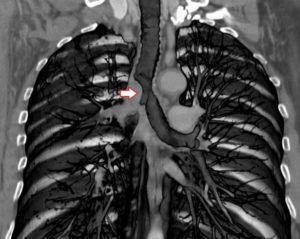

- Получение рентгеновского снимка, компьютерной и магнитно-резонансной томографии — на них явно видно расширение бронхов и усиление их рисунка.

При рентгенографическом обследовании можно обнаружить затемнения, локализующиеся в бронхах.

При рассмотрении рентгенографического снимка просматривается усиленный рисунок бронхиального дерева, просвет бронхов сужен, образуются бронхоэктазы.

На рентгенограммах просматривается расширение малых бронхов, явно заметно сужение их просвета, наблюдаются бронхоэктазы в большом количестве.

Рентгенограмма показывает усиление рисунка бронхиального дерева, сужение просвета бронхов, образование бронхоэктаз.

На рентгенологических снимках расширения видны даже в мелких бронхах, хорошо просматриваются их патологические сужения, множественные бронхоэктазы.